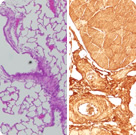

Investigadores del Instituto Municipal de Investigación Médica (IMIM-Hospital del Mar) han comprobado la relación entre el estrés celular oxidativo y la pérdida de masa muscular que se da en la fase final de algunas enfermedades como el cáncer. Estudios anteriores realizados por el mismo grupo ya habían aportado datos sobre las implicaciones del estrés oxidativo en la pérdida de pérdida y disfunción muscular en diversas enfermedades crónicas, pero ahora es la primera vez que se ha realizado un estudio experimental comparativo entre diferentes tipos de músculos de las extremidades y el miocardio en animales con caquexia cancerosa.

Se trata de un estudio colaborativo, llevado a cabo por investigadores del IMIM-Hospital del Mar y de la Facultad de Biología de la Universidad de Barcelona, encabezado por Esther Barreiro, Francesc López-Soriano, y Josep M. Argilés. Los investigadores han desarrollado un trabajo experimental exhaustivo en un modelo de base animal en que han estudiado la naturaleza de las alteraciones oxidativas producidas en diferentes tipos de músculos: músculos periféricos de diferente composición fibrilar y músculo cardiaco, así como el alcance de estas modificaciones oxidativas. Para alcanzar estos objetivos, se ha utilizado un modelo clásico de caquexia cancerosa, el hepatoma ascítico de Yoshida, que induce caquexia en pocos días, junto con los correspondientes animales control.

Este estudio ha permitido demostrar que el estrés oxidativo está probablemente implicado en el menor tamaño de las fibras musculares rápidas tipo II de los músculos de las extremidades, sobre todo el gastrocnemius, en las ratas portadoras del tumor con caquexia. El estrés oxidativo es el desequilibrio entre la producción de oxidantes y de antioxidantes en las células, pudiendo ser, en parte, responsable del deterioro y del envejecimiento celular. El exceso de oxidantes, no tamponado por los antioxidantes, puede dañar diversas estructuras celulares como el ADN, induciendo posibles mutaciones, los lípidos, y las proteínas, contribuyendo, en este caso, a su inactivación, especialmente las enzimas, y/o a su mayor degradación. Ésta es claramente nuestra hipótesis de trabajo: el estrés oxidativo incrementa la susceptibilidad de las proteínas a ser degradadas por los sistemas proteolíticos celulares.

Los autores concluyen que en este modelo experimental de caquexia cancerosa, los niveles de estrés oxidativo de proteínas estructurales y de enzimas responsables del metabolismo de la glucosa, de la hidratación del dióxido de carbono, y de la reserva muscular de ATP estaban significativamente más aumentados en los músculos periféricos y el miocardio de los animales afectos que en las ratas control. Además los niveles de proteínas oxidadas resultaron ser también significativamente superiores a las fibras tipo II de los gastrocnemius de las ratas caquécticas que en los animales control, coincidiendo con una reducción significativa de los tamaños de las mencionadas fibras en los animales caquécticos. Estos hallazgos llevan a la conclusión final de que el estrés oxidativo esté directamente implicado en la atrofia de las fibras rápidas de los músculos de las extremidades en la caquexia cancerosa, con las posibles consecuentes implicaciones terapéuticas que se pueda derivar en futuros trabajos del grupo.